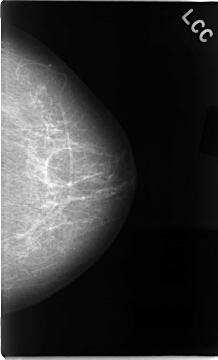

C_0022_1.LEFT_CC

LEFT_CC LINES 4672 PIXELS_PER_LINE 2824 BITS_PER_PIXEL 12 RESOLUTION 50 NON_OVERLAY

TOTAL_ABNORMALITIES 1

ABNORMALITY 1

LESION_TYPE CALCIFICATION TYPE AMORPHOUS DISTRIBUTION CLUSTERED

LESION_TYPE MASS SHAPE IRREGULAR MARGINS MICROLOBULATED

ASSESSMENT 5

SUBTLETY 5

PATHOLOGY MALIGNANT